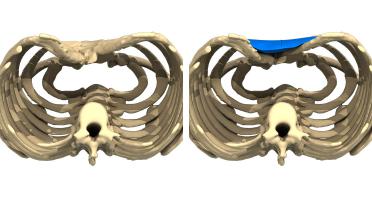

La tecnica di impianto su misura è una tecnica chirurgica minore che consiste nel riempire la concavità creata dal Pectus con un impianto personalizzato. Si tratta di un intervento rapido, a basso rischio, con un risultato immediato e una breve convalescenza.

In questa pagina, troverà i risultati di questa operazione a seconda del tipo di Pectus : mediale, asimmetrico, più o meno profondo o lungo.

Tipo 1 : Mediano, profondo e simmetrico,